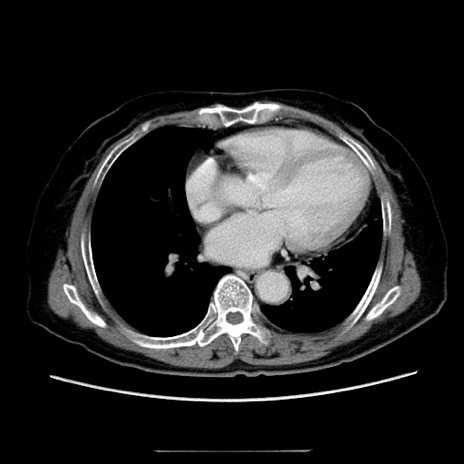

症例5(横断像)

【症例】70歳代女性

【主訴】お腹が張る

【現病歴】1週間くらい前から腹部膨満の自覚あり。昨日夜から増悪したため、本日救急外来受診。

【身体所見】意識清明、BT 36.5℃、BP 165/106mmHg、HR 80bpm、SpO2 98%、腹部:膨満、軟、自発痛・圧痛なし、触診にて不快感あり、腸蠕動音:減弱

【データ】WBC 12600、CRP 1.04